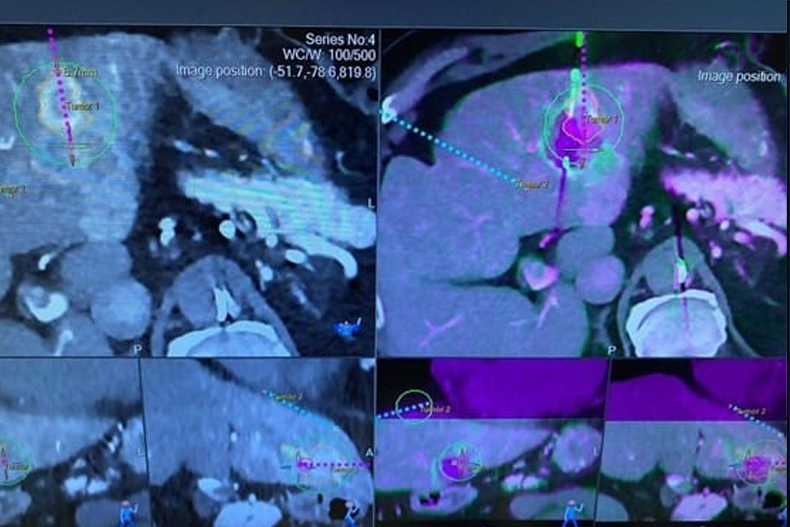

The Royal Marsden is a world-renowned oncology hospital, and its exclusive focus on oncological patients exposed me to a wide spectrum of interventional oncology procedures. These included robotic ablations of the liver, lung, and kidney; robotic biopsies; biliary interventions; transarterial embolizations; urinary interventions; and various ablative therapies. In particular, I broadened my knowledge of ablation modalities such as microwave ablation, radiofrequency ablation, and cryoablation, gaining valuable insight into how each technique is selected and applied according to patient- and tumor-specific factors. One especially innovative technique was transcatheter CT hepatic angiography for liver ablation, which allows highly precise delineation of ablation margins and demonstrates how advanced imaging enhances both precision and safety in interventional oncology.

Beyond routine procedures, I was able to observe complex ablations in detail. These highlighted how factors such as tumor size, location, and proximity to vital structures influence both the choice of ablation modality and the overall therapeutic approach. Watching the planning and execution of these cases gave me a deeper understanding of how interventional radiology can be tailored to maximize efficacy while ensuring patient safety.